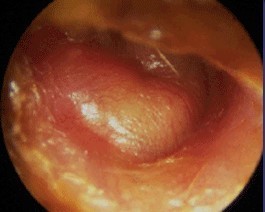

Question 2 : Voici l’otoscopie controlatérale à droite (figure 3). Quel est votre diagnostic ?

Il s’agit ici d’une OMA simple. Elle est non perforée car on ne voit pas de pertuis ni d’otorrhée purulente. Elle n’est pas phlycténulaire car le tympan est lisse et régulier, sans vésicule.